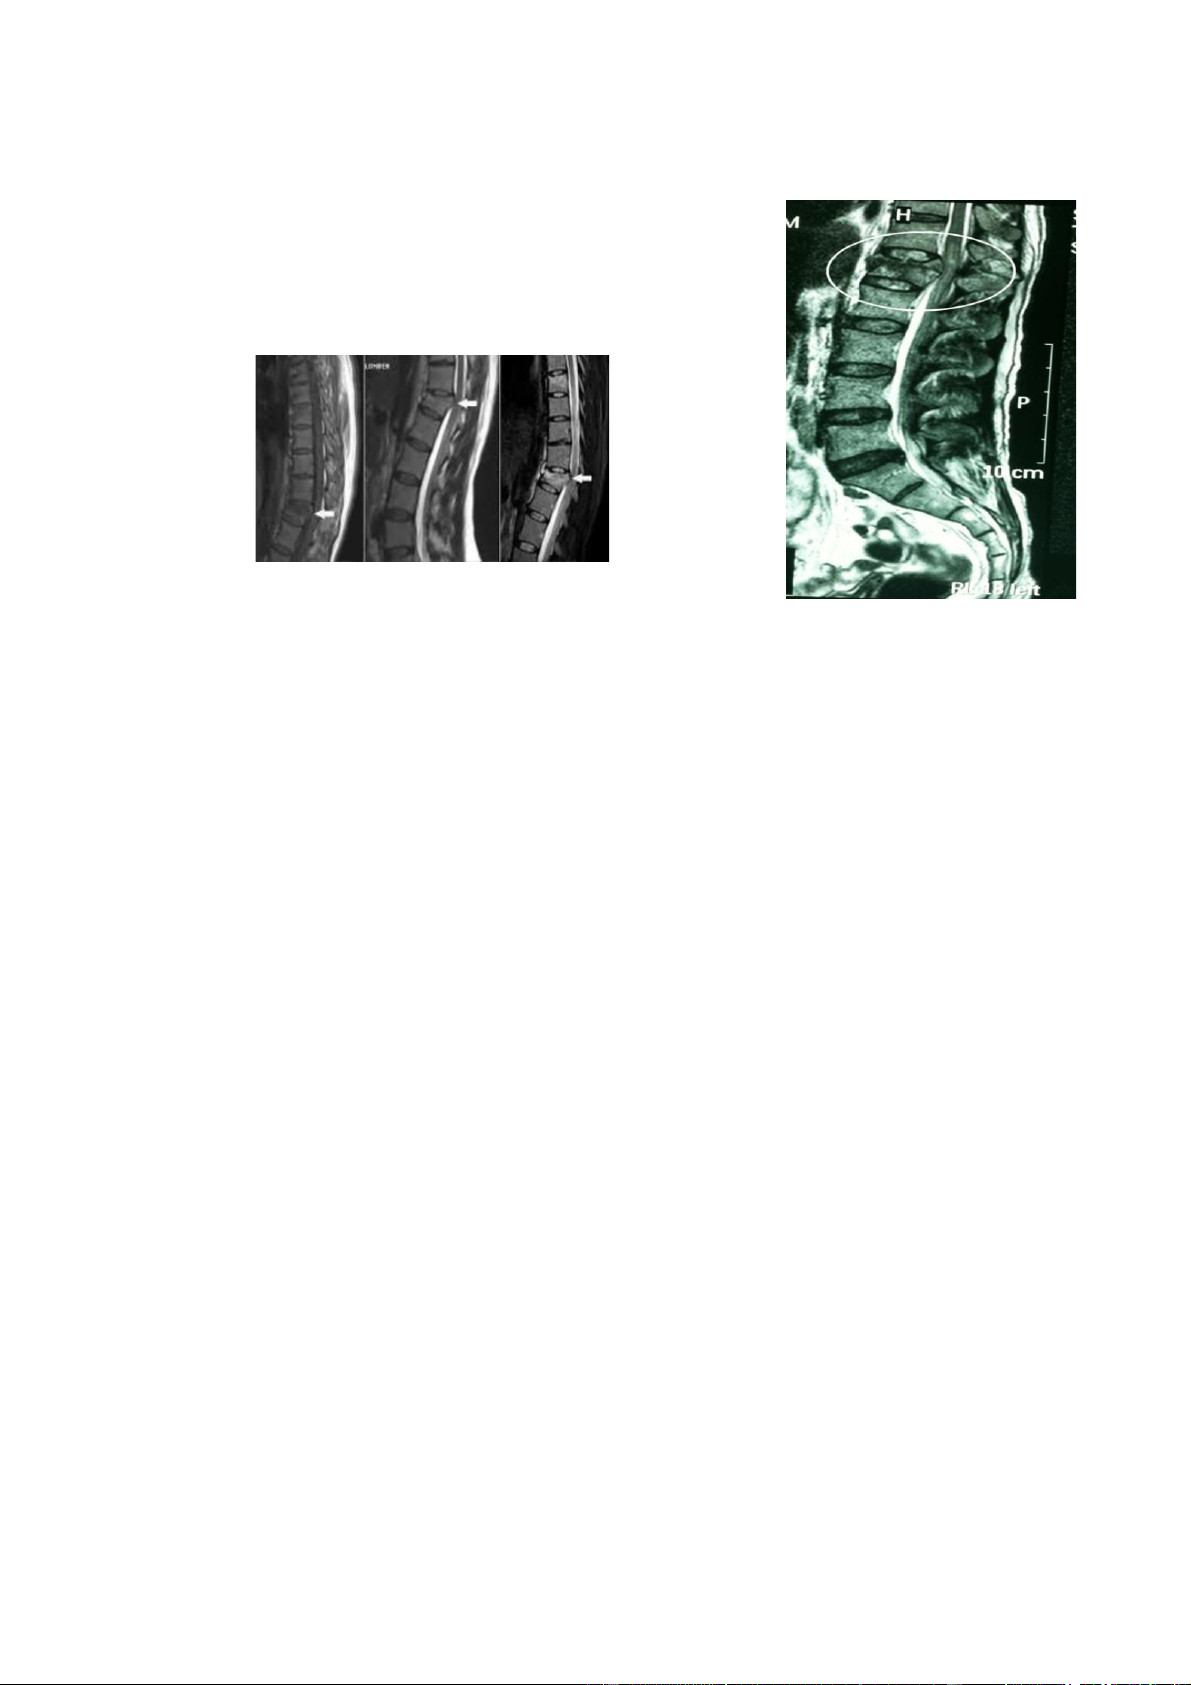

Dựa vào hình ảnh chụp cắt lớp ể phân loại (theo Denis). • Chụp cộng hưởng từ Để xác ịnh ược chính xác và trực tiếp thương

tổn phần mềm, thương tổn thần kinh. Ngoài ra, còn xác ịnh thương tổn trong tuỷ (tụ

máu hay dập tuỷ), các thương tổn dây chằng và ĩa ệm. Nhược iểm: lOMoAR cPSD| 22014077

- Nhận dạng tổn thương xương kém hơn cắt lớp vi tính.

- Không chụp ược bệnh nhân có kim loại trong người.

- Thời gian chụp lâu, chưa ược sử dụng rộng rãi trong cấp cứu. 6. Điều trị Mục tiêu iều trị: - Nắn cố ịnh thương tổn xương.